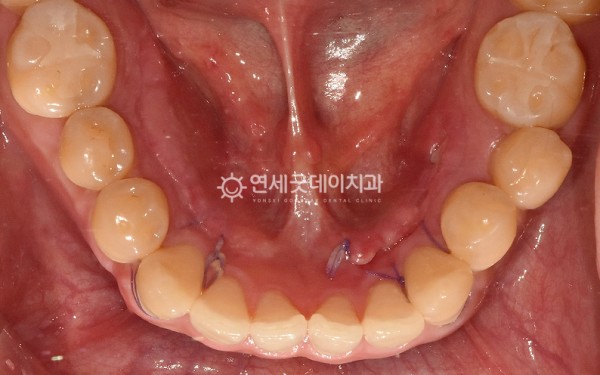

하악골융기가 신경쓰이고

불편하다는 주소로

내원해주신 30대 남성분이십니다.

환자분은 하악골융기 하방으로

음식물이 많이 끼고 신경쓰이는 듯한

불편함을 호소하셨으며

혀 밑으로 양쪽에 크기가 큰 토러스가 관찰되었습니다.

하악골융기 제거 직후로,

울퉁불퉁한 골융기가 제거되고

잘 아물수 있도록 깔끔히 봉합해드렸으며